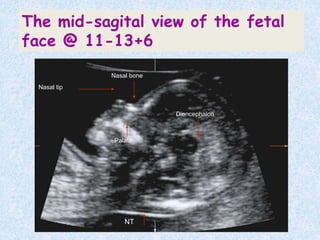

The mid-sagital view of the fetal

face @ 11-13+6

HOW TO MEASURE NASAL

BONE?

 Fetus should face

transducer.

 Face & thorax

occupy whole image.

 Angle of insonation-

90`.

 Presence of equal(=)

sign.

 If bottom part of

equal sign is

missing-absent

nasal bone.